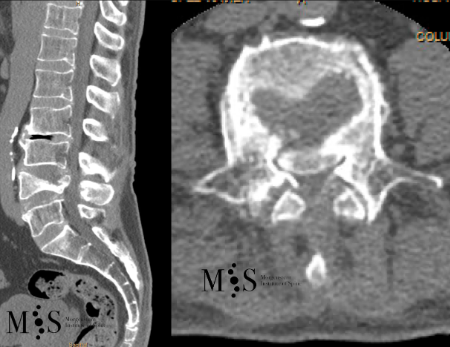

Resecció (corpectomia) i reconstrucció vertebral de fractures vertebrals complexes i conminutes

En els casos de les fractures més greus, com les fractures conminutes i les fractures d’esclat, un fragment del cos vertebral pot ficar-se dins del canal medular, provocant una compresió de les estructures neurològiques (estenosi del canal medular).

Quan amés n’hi ha un compromis neurològic, s’haruá de realitzar una resecció parcial o total del cos vertebral fracturat (corpectomia) per després reconstruir-lo reconstrucción mitjantçant d’una caixa somàtica expandible. La reconstrucció es sol completar amb una artrodesi percutànea instrumentada i cementada dels nivells adjacents a la fractura. La resecció de la vèrtebra (corpectomia) permet extrahir el fragment d’os qu’es trova al canal medular i lliberar les estructures neurològiques afectades. La reconstrucció amb una caixa somàtica permit descarregar la carga del pacient sobre la fractura i treure el dolor que aquesta li provoca.

Cas clínic d'una resecció (corpectomia) i reconstrucció vertebral lumbar en una fractura esclat de nivell L4.